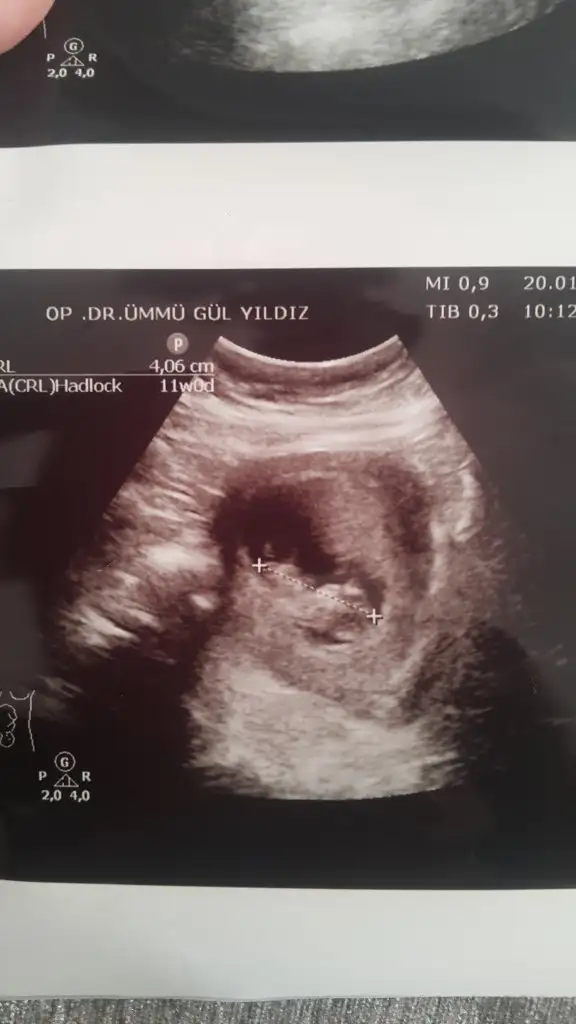

dr soylemeden siz gorun genital nub teorisi ( bebegin cinsiyeti)

Screenshot_20200120-154357.webp

mrhaba lütfen yorumlarmisiniz sizce kızmı erkekmi bi arkadas icin soruyorum